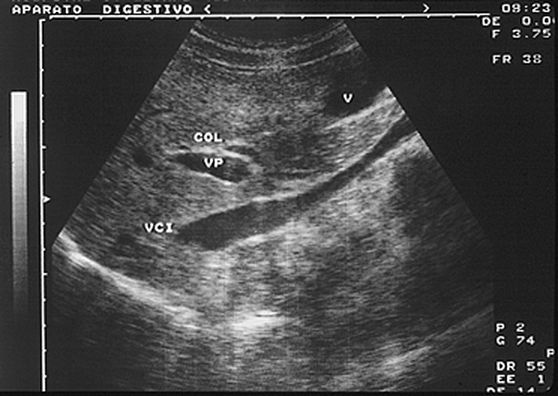

1.1. Anatomía normal

Dr. Mariano Gómez Rubio (Getafe)